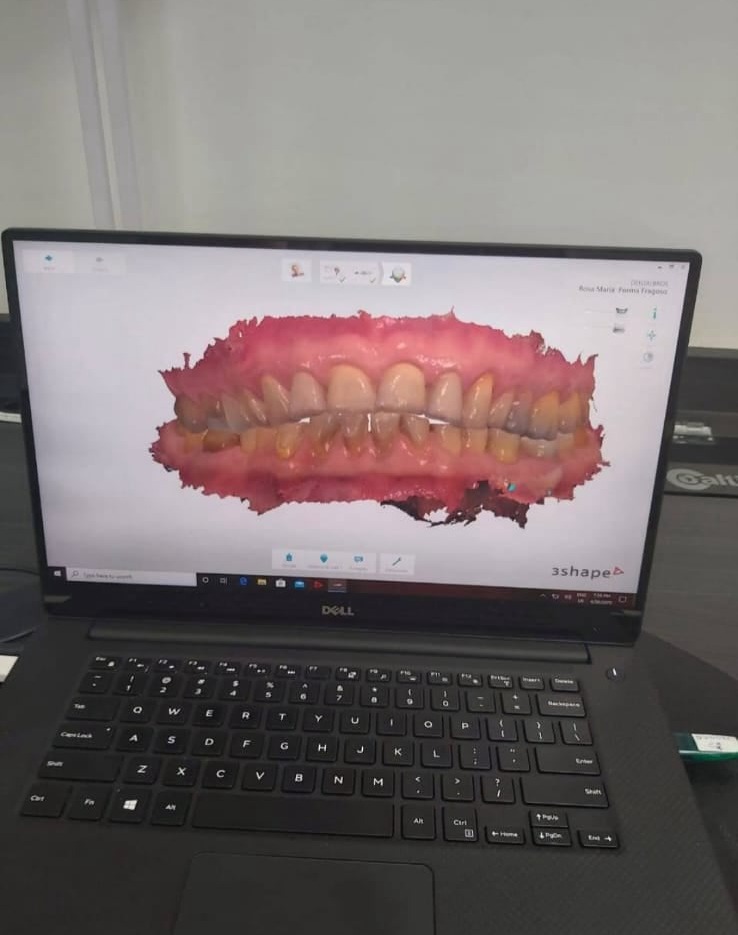

Consiste em uma anamnese detalhada para saber o histórico do paciente e da lesão, um exame físico/clinico analisando todas as estruturas da cavidade bucal, sistema estomatognatico, cabeça e pescoço. Apenas caso seja necessário é realizada uma biopsia, que é a remoção parcial ou total da lesão para ser encaminhada pra exame histopatológico.

Ainda que esse nome sugira "estômago", quem cuida de estômago é o gastroenterologista. O prefixo "estomato" significa boca e o sufixo "logia" significa estudo, e dessa maneira, a estomatologia é a especialidade de odontologia que se ocupa das alterações que acontecem na boca.